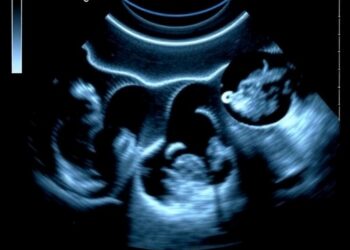

In the rapidly evolving field of medical imaging, the precision and efficiency of diagnostic tools are paramount, particularly in ophthalmology, ...